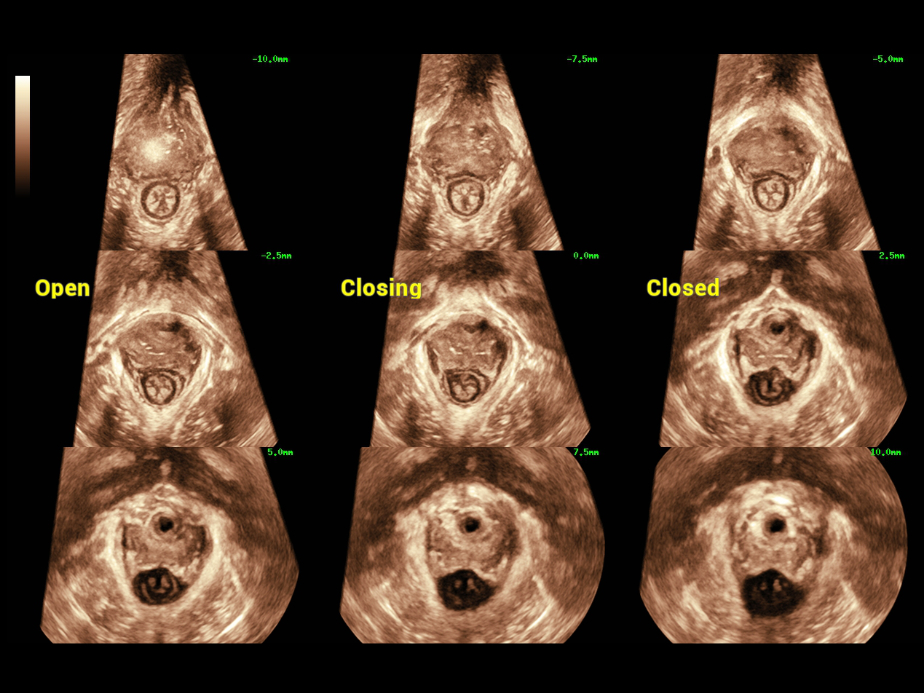

In the ultrasound diagnosis of FPFD, doctors promote a global approach to a comprehensive and accurate diagnosis of the anterior, middle and posterior pelvic compartments, in which it includes a large number of 2D measurement requirements, 3D/4D imaging and evaluation requirements, etc. The exam process is time-consuming and inconvenient, with high demands on imaging modes and fast measurements.

Nuewa provides automatic 2D measurements for the pelvic compartment and an intelligent volume evaluation system, including automated evaluation for levator hiatus and multi-section analysis with automatic measurements.